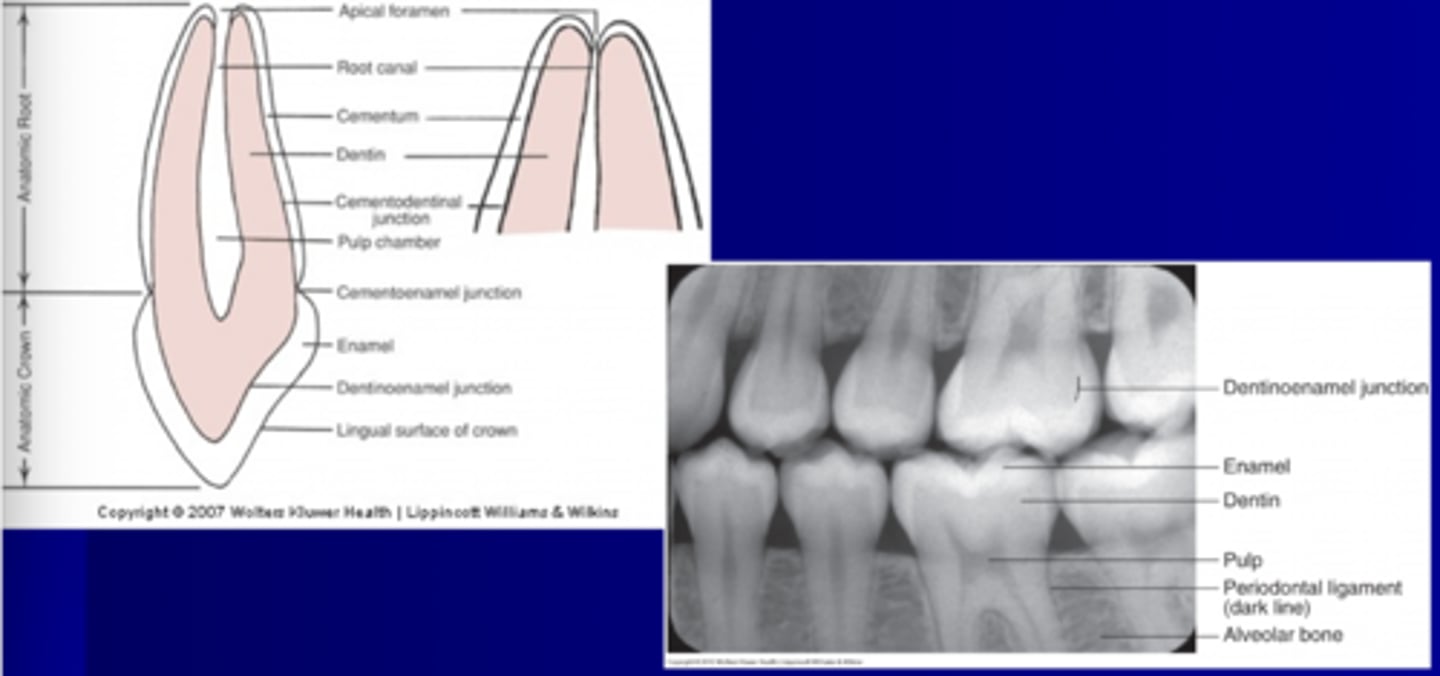

Clinical Crown

Whats seen, everything

Clinical Root

DOES not show

Anatomical root

Covered in cementum

Anatomical Crown

Covered by enamel

External morphology of the anatomical root

CEJ separates the anatomic crown from the anatomic root